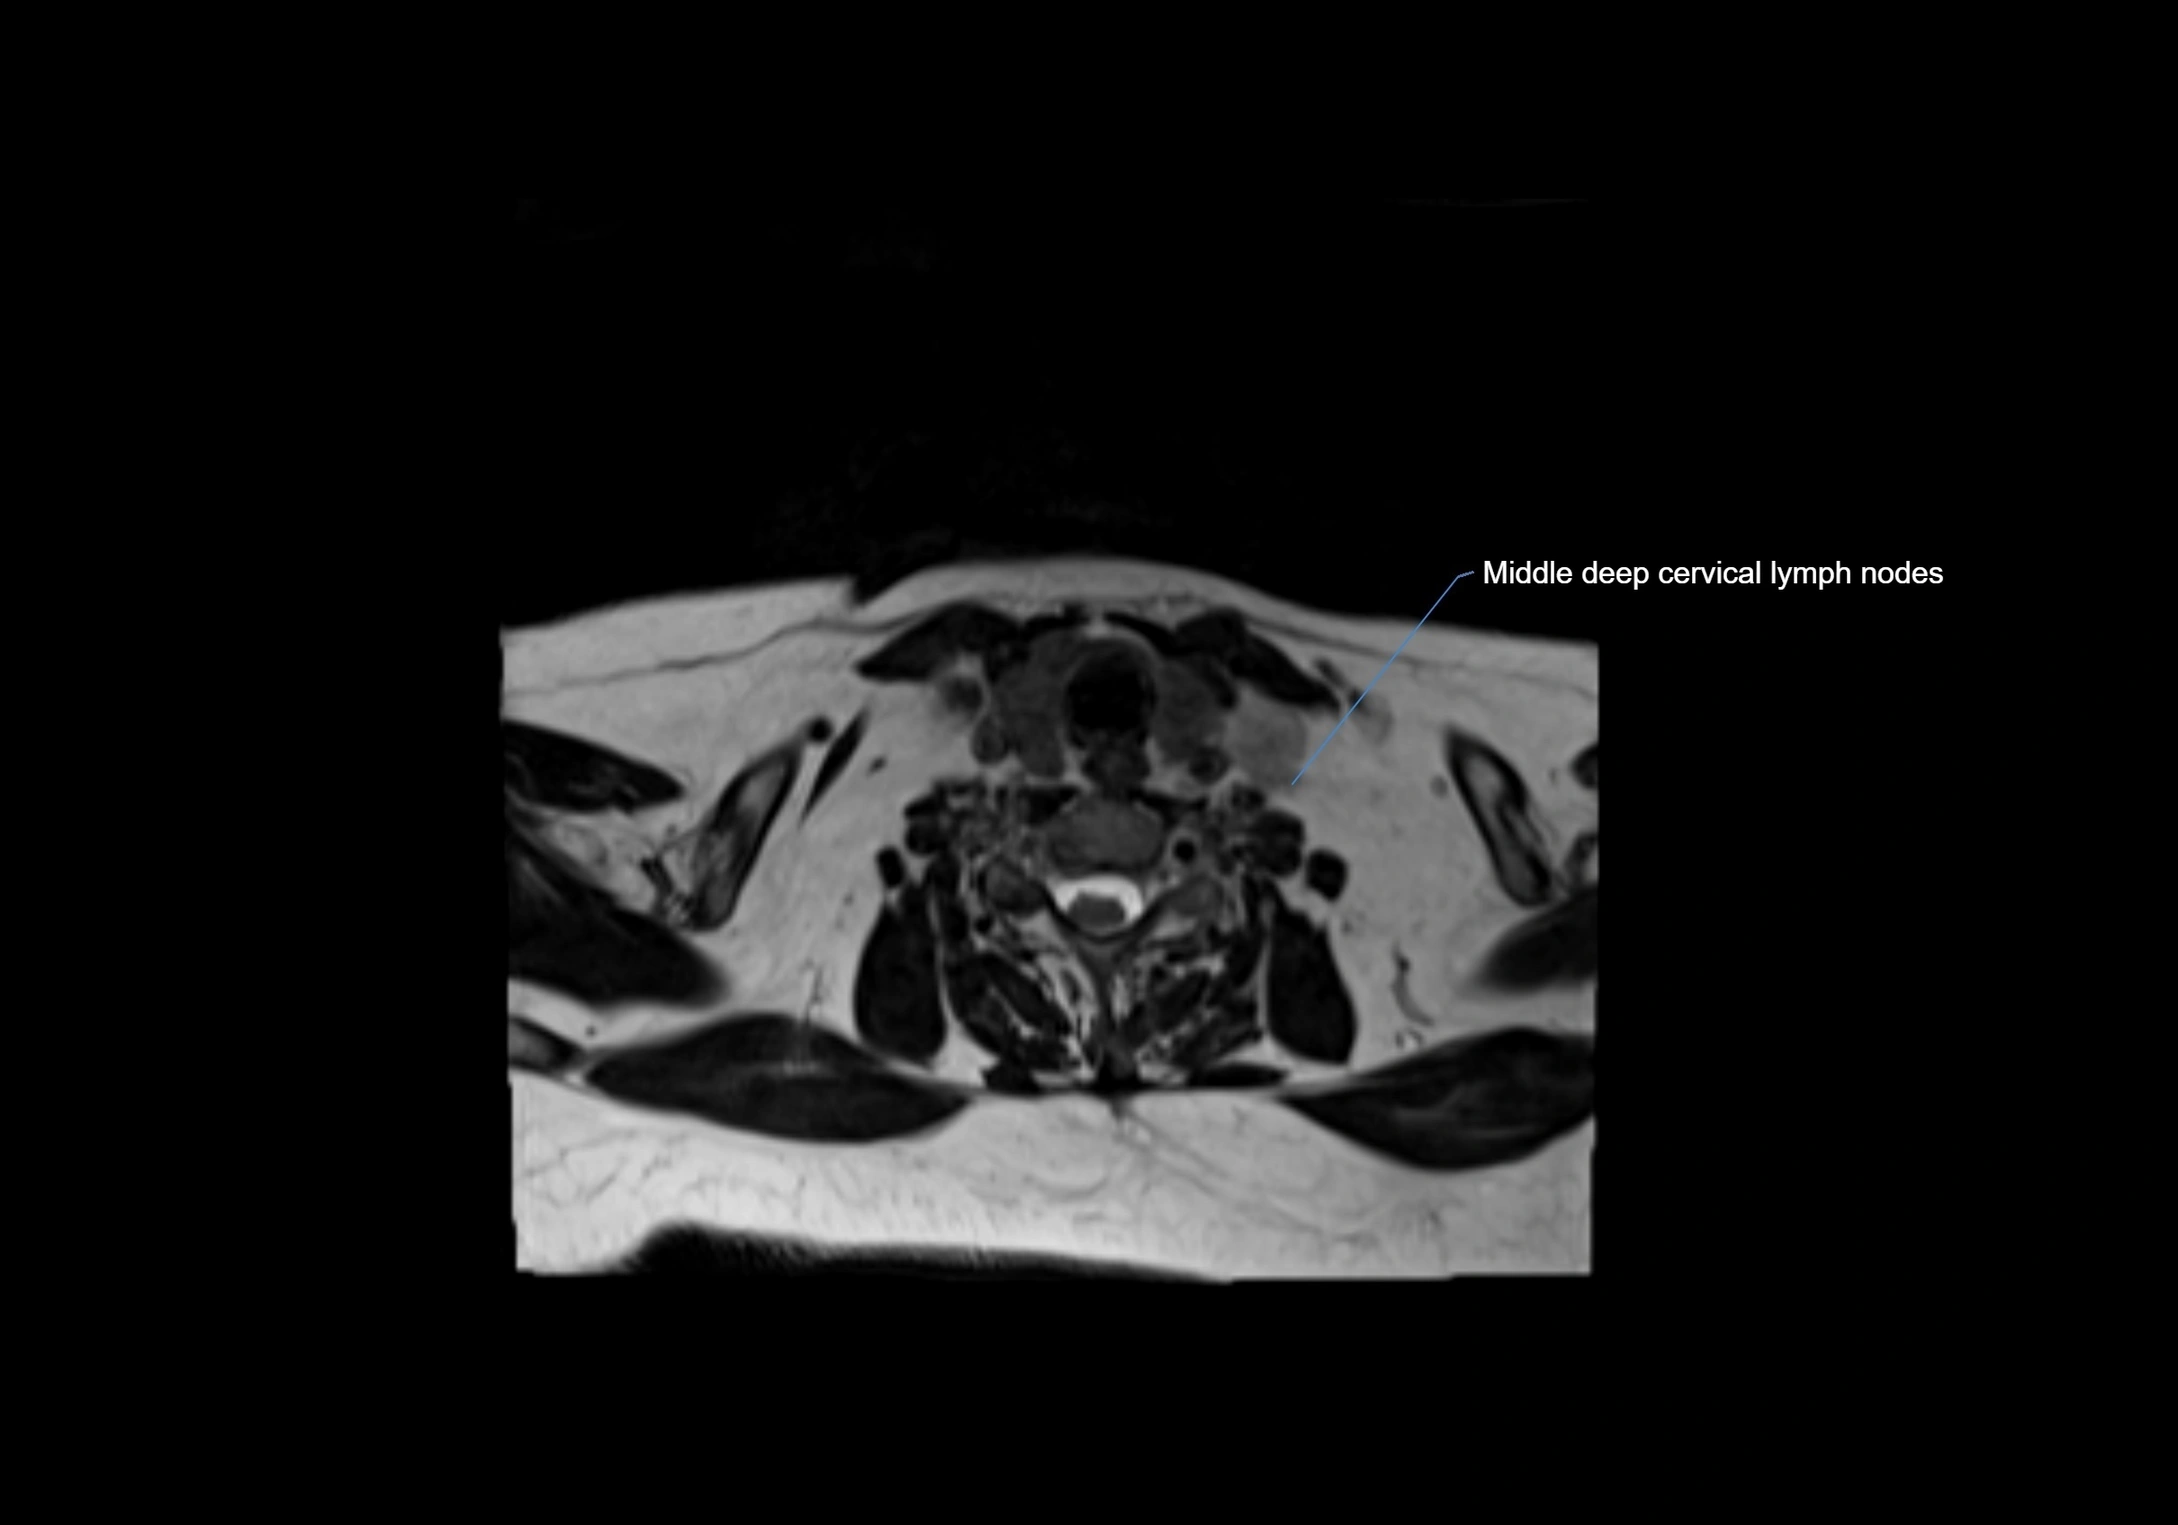

MRI Appearance

T1-weighted images:

• Normal accessory nodes appear as small, oval hypointense to intermediate signal structures within subcutaneous fat

• Surrounded by hyperintense fat, enhancing contrast for visualization

• Pathological nodes may appear enlarged or rounded, sometimes with cortical thickening

T2-weighted images:

• Nodes show intermediate signal, with surrounding fat bright

• Useful for detecting edema, inflammation, or infiltration

• Fatty hilum may appear slightly hyperintense relative to cortex

MRI images

image